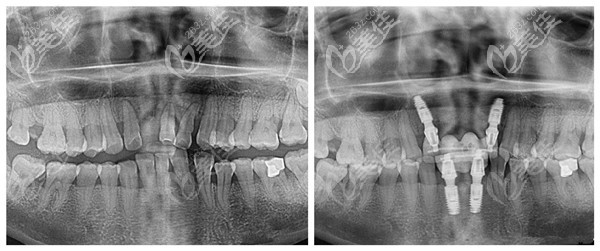

牙齒疾病或者是外在因素,都會導(dǎo)致牙齒缺失,那就需要做種植牙才能改善。一直聽說石家莊趙翠彩做即刻負重修復(fù)效果不錯,價格還不貴,來看下真實案例就知道。